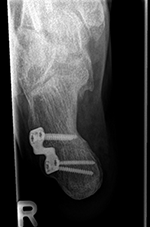

Aufrichtung durch Stabilisierung

Die Stabilisierung des unteren Sprunggelenkes (Arthrodese) ist eine effektive Methode zur Korrektur des fortgeschrittenen Knick-/Senkfußes, wenn hier bereits als Folge der Fehlstellung Arthrose aufgetreten ist. Dieser Eingriff wird ebenfalls oft mit weiteren Maßnahmen der Fußinnenseite kombiniert. Einige Monate nach der Operation ist in der Regel von außen am Gangbild nicht zu erkennen, dass ein Fußgelenk versteift wurde.

Minimal invasive Fußchirurgie

Die Durchtrennung der Ferse erfolgt über einen kleinen Hautschnitt von ca. 2-3mm. Zur Stabilisierung ist eine Schraube notwendig, die über einen weiteren Schnitt von ca. 7-8mm erfolgt.